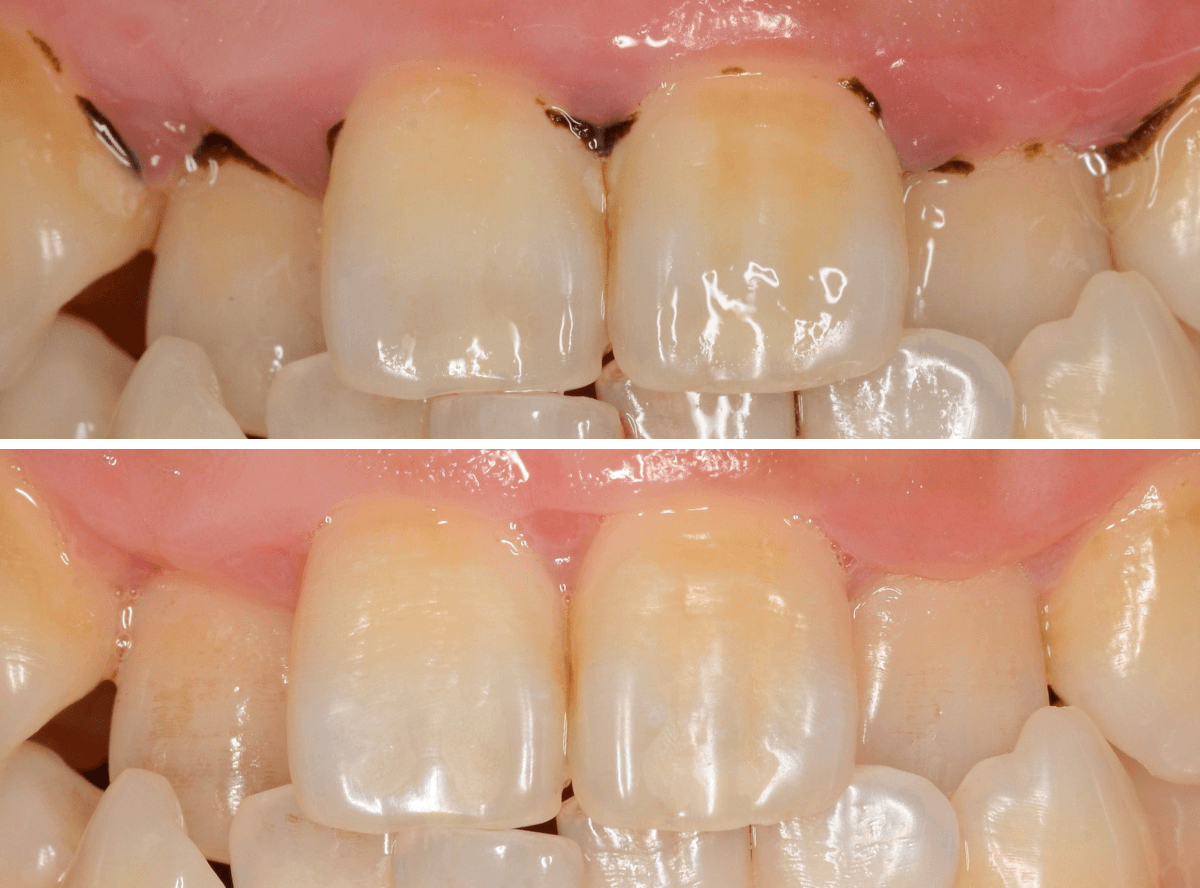

Case.1

「口臭が気になる」という理由で来院された患者さんです。

何度か来院され、歯石除去や歯ブラシ指導をしているのですが、まだまだ、徹底されていないのがわかります、もう少し頑張ってほしい(><)

歯肉の縁が赤く腫れています。こういった歯肉の中には歯石がたまっている可能性が大です。

この歯肉の中の見えない歯石は、歯肉の上の歯石よりも、歯周病の原因になります。

歯周病は痛みなどの自覚症状に乏しく、気づけば完全に治らない状態まで進んでいる事も多いので早期発見・治療が大切です。

保険診療では、歯石除去は一日で治療できる範囲が限られています。

今回は、上の前歯の部分の歯肉の中の歯石除去をしました。

歯石除去後です。

この状態を長く維持してもらう必要があります。